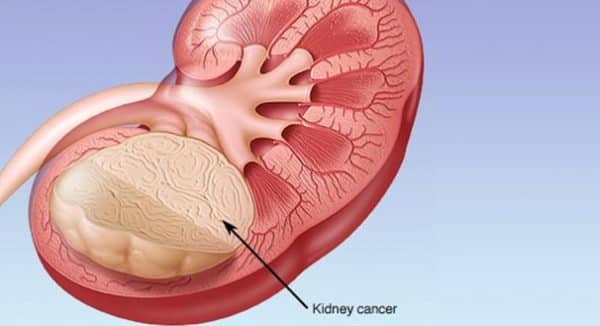

Τα υγιή κύτταρα δεν συναντούν εμπόδια στην μεταλλαγή τους σε καρκινικά εξαιτίας ενός γονιδίου που ονομάζεται von Hippel-Lindau (VHL). Μάλιστα, το Νόμπελ Φυσιολογίας ή Ιατρικής του 2019 απονεμήθηκε στους επιστήμονες που ανακάλυψαν ότι το VHL ήταν μέρος του συστήματος ανίχνευσης οξυγόνου στο κύτταρο. Κανονικά, το VHL διασπά μια άλλη πρωτεΐνη που ονομάζεται HIF. Κατά συνέπεια, όταν το VHL μεταλλάσσεται, το HIF συσσωρεύεται και προκαλεί μια ασθένεια που ονομάζεται σύνδρομο VHL, στην οποία τα κύτταρα αντιδρούν σαν να τους λείπει οξυγόνο παρά το γεγονός ότι υπάρχει οξυγόνο. Το σύνδρομο VHL αυξάνει σημαντικά τον κίνδυνο όγκου, καλοήθους και κακοήθους. Ο καρκίνος του νεφρού που προκαλείται από το σύνδρομο VHL έχει κακή πρόγνωση, με ποσοστό πενταετούς επιβίωσης μόλις 12%.

Στην παρούσα μελέτη, οι ερευνητές εξέτασαν την περιεκτικότητα σε πρωτεΐνες των καρκινικών κυττάρων από ασθενείς με διαφορετικές παραλλαγές του συνδρόμου VHL και πώς διέφεραν από μια άλλη ομάδα ατόμων με μια ειδική μετάλλαξη VHL που ονομάζεται Chuvash, μια μετάλλαξη που εμπλέκεται σε διαταραχές ανίχνευσης υποξίας χωρίς καμία ανάπτυξη όγκου. Όσοι είχαν τη μετάλλαξη Chuvash VHL είχαν φυσιολογικά μιτοχόνδρια στα κύτταρά τους, ενώ εκείνοι με μετάλλαξη στο σύνδρομο VHL είχαν λίγα. Για να αυξήσουν την ποσότητα μιτοχονδριακού περιεχομένου στα καρκινικά κύτταρα των νεφρών που σχετίζονται με το VHL, οι ερευνητές αντιμετώπισαν τους όγκους με έναν αναστολέα μιας μιτοχονδριακής πρωτεάσης που ονομάζεται LONP1. Τα κύτταρα στη συνέχεια έγιναν ευαίσθητα στο αντικαρκινικό φάρμακο sorafenib, στο οποίο προηγουμένως αντιστέκονταν. Σε μελέτες σε ποντίκια, αυτή η συνδυαστική θεραπεία οδήγησε σε μειωμένη ανάπτυξη όγκου.